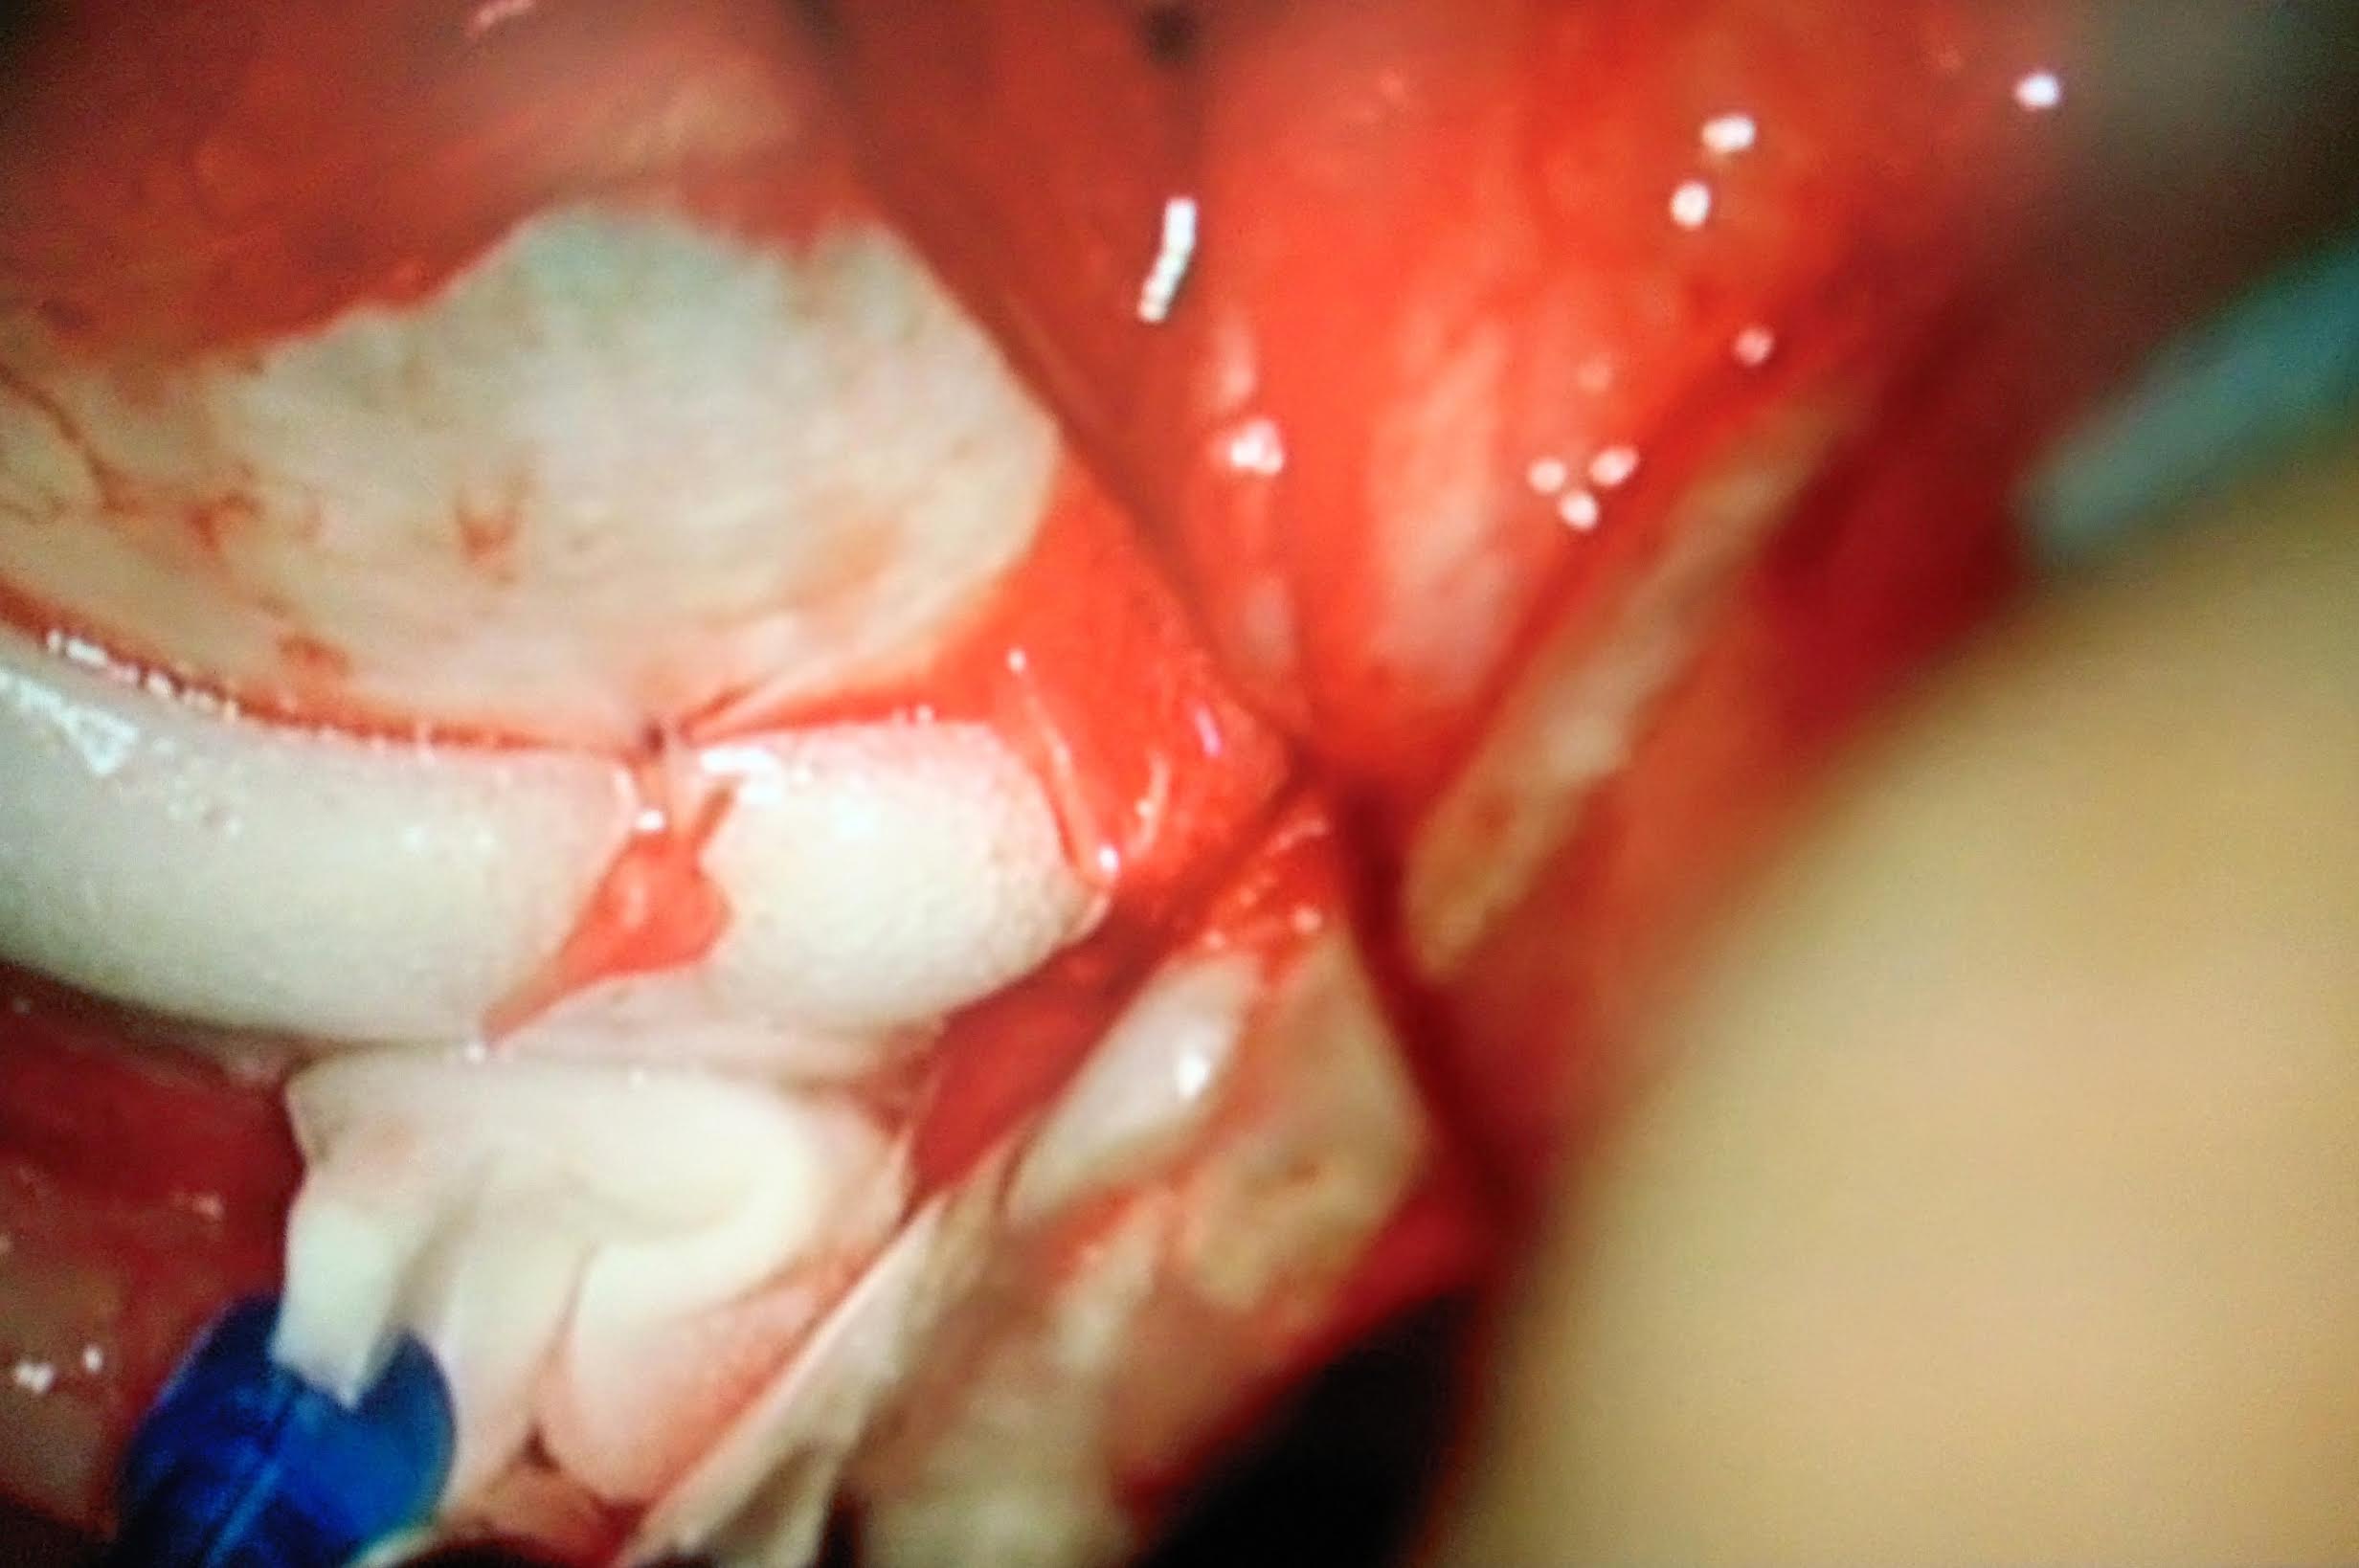

10 Intervento di chirurgia episclerale per distacco di retina

Paziente di 67 anni riferisce forte calo visivo nell'occhio destro da alcuni giorni, l'obiettività oculistica era la seguente:

fundus: distacco di retina macula off (coinvolgente anche la macula) da ore 3 a ore 9 circa con duplice rottura retinica ore 6 circa

Effettuata chirurgia episclerale (cerchiaggio)

1) Peritomia congiuntivale su 360° isolamento dei muscoli retti e posizionamento dei fili di trazione) foto 1

2) Posizionamento di fibra ottica per esplorazione del fundus con sistema biom foto  2

3) Localizzazione delle rotture retiniche e criotrattamento foto 3

4) Cerchiaggio con spugna in silicone foto 4

5) Puntura evacuativa e drenaggio del fluido sottoretinici foto  5

6) Controllo indentazione delle rotture foto 6

7) Sutura congiuntivale foto 7

Il decorso post operatorio è stato regolare